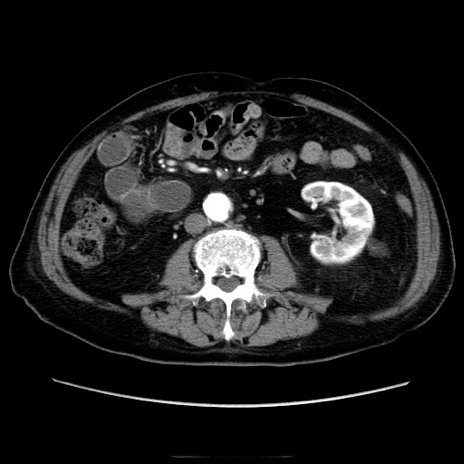

症例21(横断像)

【症例】70歳代男性

【主訴】腹痛

【現病歴】肝硬変・肝細胞癌にてかかりつけの方。約9時間前に食後より腹痛出現。症状が徐々に増悪し、嘔吐出現したため来院。

【既往歴】肝硬変、肝細胞癌(RFA、TACE後)

【身体所見】意識清明、表情苦悶様、BT 36℃、BP 129/78mmHg、P 88bpm、SpO2 97%(RA)、右上腹部から心窩部にかけて圧痛あり、反跳痛なし、筋性防御あり。

【データ】WBC 5800、CRP 0.16